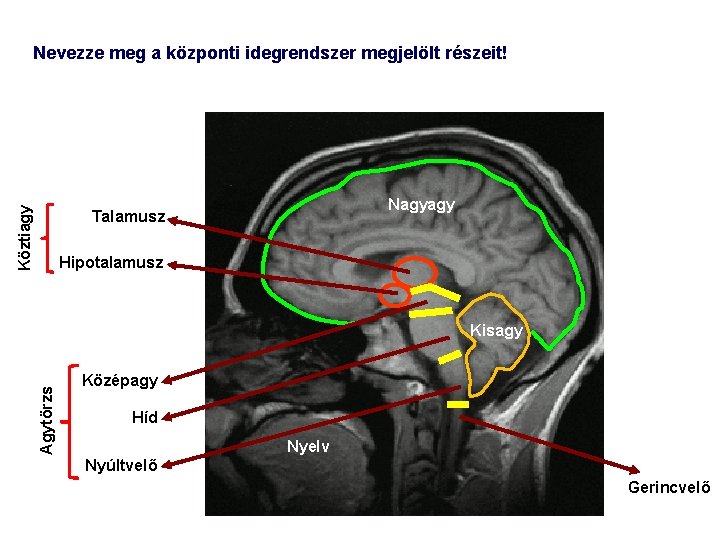

Köztiagy Nevezze meg a központi idegrendszer megjelölt részeit! Nagyagy Talamusz Hipotalamusz Agytörzs Kisagy Középagy Híd Nyelv Nyúltvelő Gerincvelő